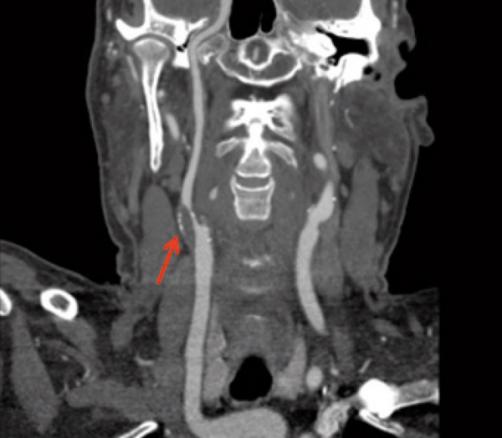

Angioscanner des troncs supra-aortiques, sténose de l'origine de la carotide interne droite associée à des calcifications